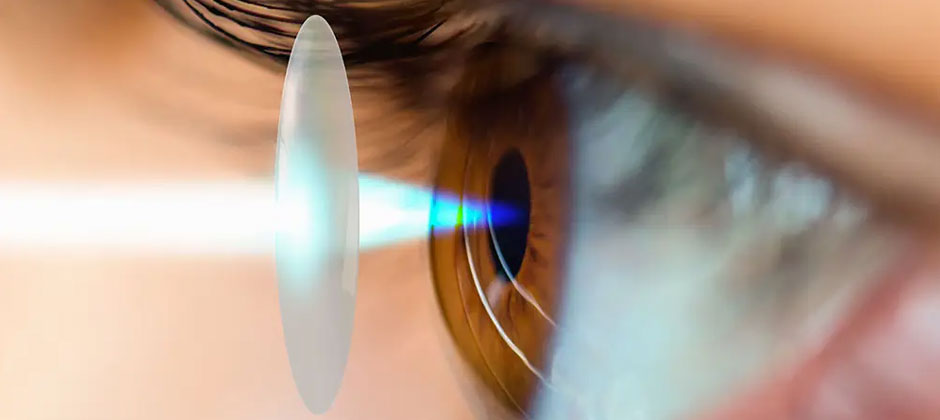

At IDR Eye Care, we are dedicated to providing comprehensive eye care to ensure that you see the world clearly and comfortably. Our team of experienced eye care professionals are committed to deliver personalized care in a welcoming and state-of-the-art environment.

IDR EYE CARE is an eye care facility provider. We specialise in all kind of Cataract, glaucoma, retinal diseases, paediatric ophthalmology, refractive surgeries and more.